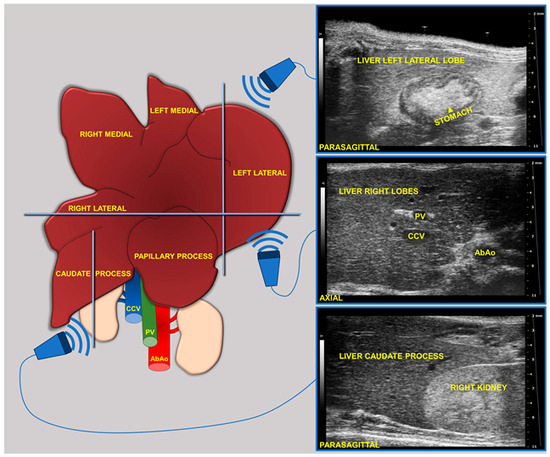

Preclinical Application of Computer-Aided High-Frequency Ultrasound (HFUS) Imaging: A Preliminary Report on the In Vivo Characterization of Hepatic Steatosis Progression in Mouse Models

Metabolic dysfunction-associated steatotic liver disease (MASLD) is one of the most common chronic liver disorders worldwide and can lead to inflammation, fibrosis, and liver cancer. To better understand the impact of an unbalanced hypercaloric diet on liver phenotype in impaired autophagy, the study [...] Read more.

Metabolic dysfunction-associated steatotic liver disease (MASLD) is one of the most common chronic liver disorders worldwide and can lead to inflammation, fibrosis, and liver cancer. To better understand the impact of an unbalanced hypercaloric diet on liver phenotype in impaired autophagy, the study compared C57BL/6J wild type (WT) and MAPK15-ERK8 knockout (KO) male mice with C57BL/6J background fed for 17 weeks with “Western-type” (WD) or standard diet (SD). Liver features were monitored in vivo by high-frequency ultrasound (HFUS) using a semi-quantitative and parametric assessment of pathological changes in the parenchyma complemented by computer-aided diagnosis (CAD) methods. Liver histology was considered the reference standard. WD induced liver steatosis in both genotypes, although KO mice showed more pronounced dietary effects than WT mice. Overall, HFUS reliably detected steatosis-related parenchymal changes over time in the two mouse genotypes examined, consistent with histology. Furthermore, this study demonstrated the feasibility of extracting quantitative features from conventional B-mode ultrasound images of the liver in murine models at early clinical stages of MASLD using a computationally efficient and vendor-independent CAD method. This approach may contribute to the non-invasive characterization of genetically engineered mouse models of MASLD according to the principles of replacement, reduction, and refinement (3Rs), with interesting translational implications. Full article